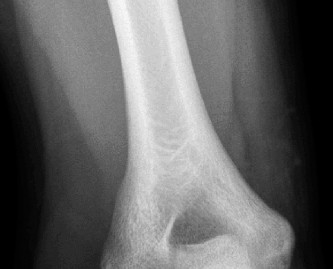

Understand common complications associated with performing surgery for scapulothoracic bursitis? CASE 33 A 42-year-old female presents to the office for follow up after sustaining a minimally displaced radial head fracture 3 months prior. She states she was initially treated in long-arm splint by the ER and did not follow up with an orthopaedic surgeon until now. Per her report, she removed the splint 4 weeks after the injury, but did not move her elbow due to pain. She now has no pain but is unable to reach that hand to her face or head. The remaining history is significant for previous ulnar nerve surgery for which she is unable to provide details. On physical examination, her upper extremity is normal except for limited flexion/extension, measured to be 80 to 50 degrees by goniometer. In addition, she has a well-healed surgical incision about the medial elbow, consistent with a previous surgery on her ulnar nerve. Her images are shown (Figs. 2–82 to 2–84).

Figure 2–82

Figure 2–83

Figure 2–84

What is the diagnosis?

- Early post-traumatic intrinsic joint contracture

- Late post-traumatic extrinsic joint contracture

- Late combined post-traumatic joint contracture

- Early combined post-traumatic joint contracture

Discussion

The correct answer is (A). Classification of post-traumatic elbow stiffness allows for better understanding of the disease and allows the clinician to treat the underlying cause of the joint contracture. Intrinsic causes include: any problem within the joint such as incongruency, loose bodies, or severe osteoarthritis. Extrinsic causes include capsular tightness, muscle contracture, heterotopic ossification, and skin contractures. Early is defined as within 6 months of the injury while late is considered to be greater than 6 months after the injury. Patients that present in the early time frame have a significantly better chance at having a good result both from nonoperative and operative treatment.